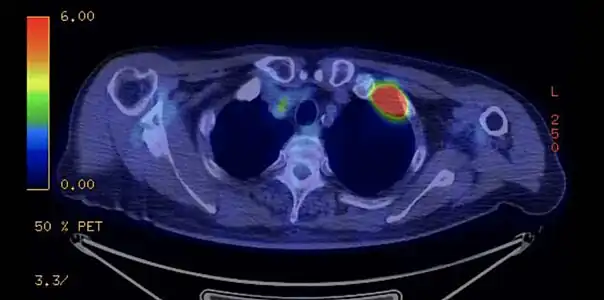

TDM d'une tumeur de Pancoast gauche envahissant l'arc antérieur de la 1re et de la 2e côte (flèche jaune).

PET-scanner du même patient[14].

Dans le cadre du bilan d'extension, le TEP scanner aide à rechercher les localisations secondaires métastatiques et à préciser l'envahissement ganglionnaire.